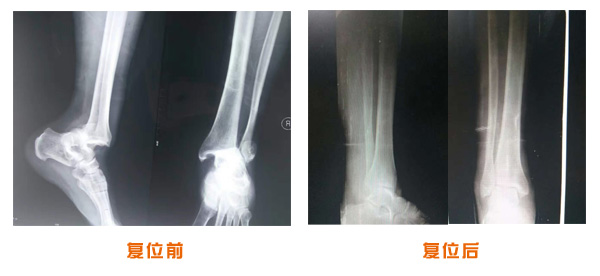

肥城市安駕莊梁氏骨科醫(yī)院是一所以梁氏手法正骨配合膏藥為特色的現(xiàn)代化專科醫(yī)院。

梁氏骨科術(shù)始創(chuàng)于清雍正年間,歷經(jīng)八代,至今已有三百年歷史。據(jù)1929年泰安縣志載“梁瑞圖先生,字增生,號蓮峰,安駕莊人,精岐黃并發(fā)明接骨,凡跌打車凡跌打車軋皮不破而碎骨者......【詳細(xì)】 |